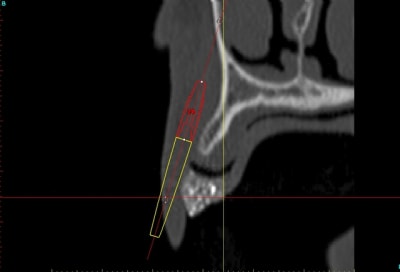

voilà, j'ai trouvé 5 mn...

le projet simplant est théorique, ça ne correspond pas à ce qui sera posé, c'était pour étude.

Fred à fait une séance d'ostéo-tension et 21 jours plus tard je me suis déplacé chez lui pour effectuer une deuxième séance, (nous avions adapté le protocole pour ce cas, 2 fois 21 jours au lieu de 40), afin de préparer le site et d'avoir une bonne connaissance du type d'os que nous allions trouver.